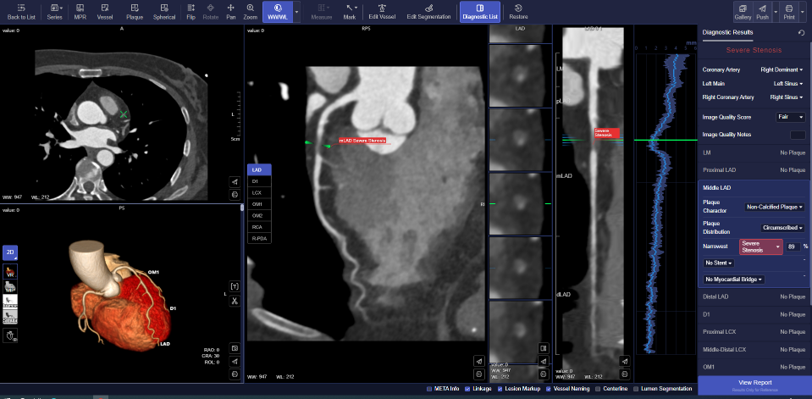

クレアボが提供する「CoronaryDoc」では、CT装置の撮像データを、人手を介さずに画像解析が可能となり、約3分以内で心臓CTの画像処理をシステム側で実施し、診断に必要な画像や構造化レポートを保存することができます[7]。また、AIアルゴリズムは冠動脈領域の描出から、狭窄が疑われる部位やプラークの識別を行い、それらの情報を構造化レポートとして作成します。

▼ 解析例

※実際の製品の表示とは異なる場合があります。